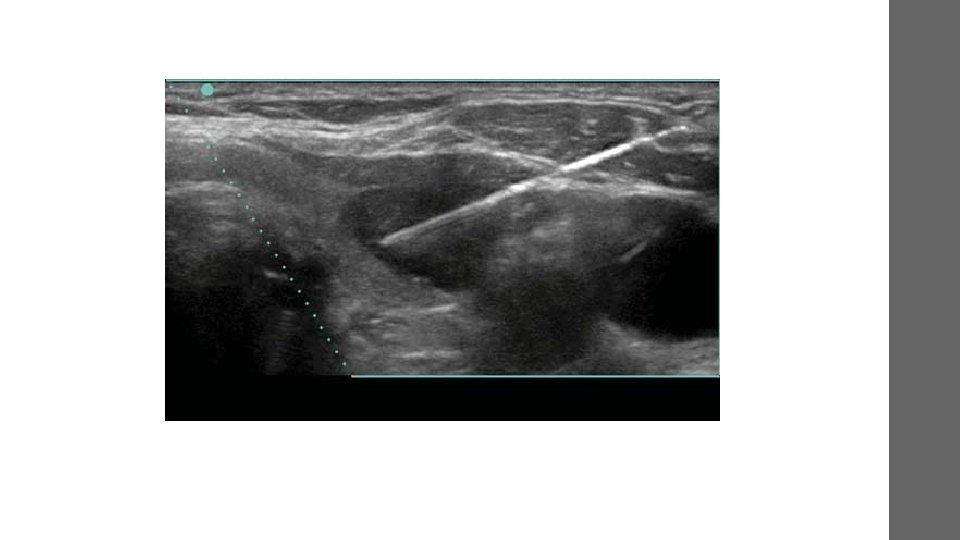

• guide procedures such as needle biopsies, in which needles are used to extract sample cells from an abnormal area for laboratory testing. • image the breasts and to guide biopsy of breast cancer • diagnose a variety of heart conditions and to assess damage after a heart attack or diagnose for valvular heart disease.